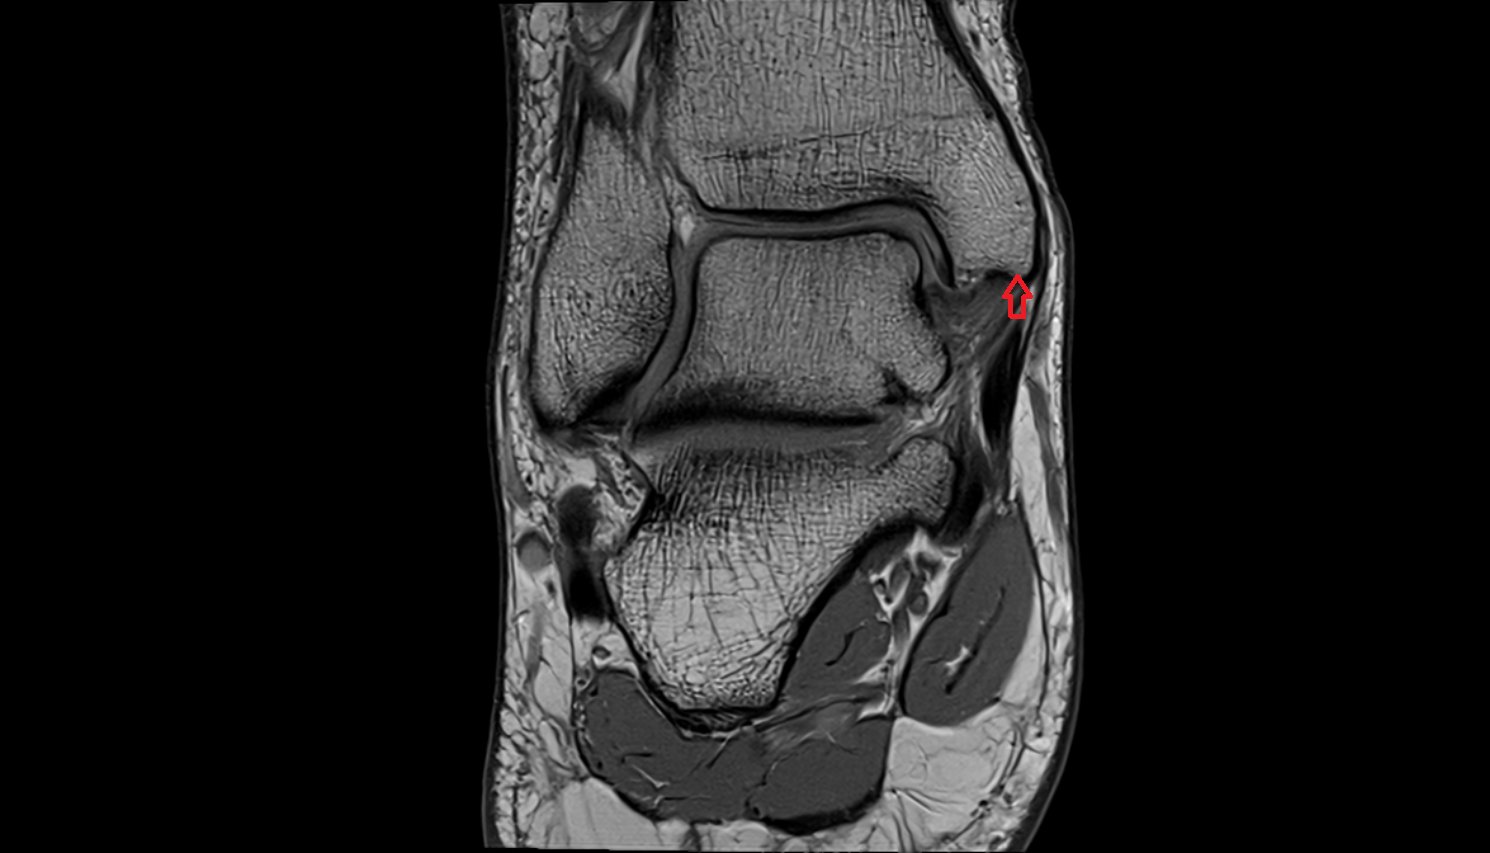

- Ankle joint

- Talus

- Body of talus

- Neck of talus

- Anterior talofibular ligament

- Posterior talofibular ligament

- Deltoid ligament complex